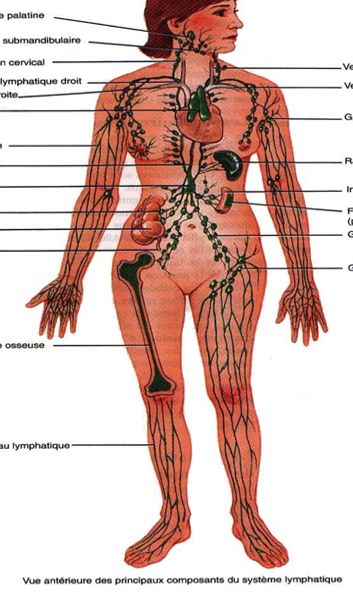

Le système lymphatique est un réseau de vaisseaux et de ganglions qui circule dans tout le corps, en parallèle du système sanguin. La lymphe est un liquide clair issu du plasma sanguin qui transporte des déchets, des protéines et des cellules immunitaires. Elle circule lentement et dépend des mouvements du corps, de la respiration et des...

Le lymphoedème est une accumulation de liquide lymphatique qui peut provoquer un gonflement des bras ou des jambes. Bien que ce soit une pathologie médicale, le drainage lymphatique manuel peut contribuer au confort, à la mobilité et au bien-être, dans un cadre légal et complémentaire aux soins médicaux.